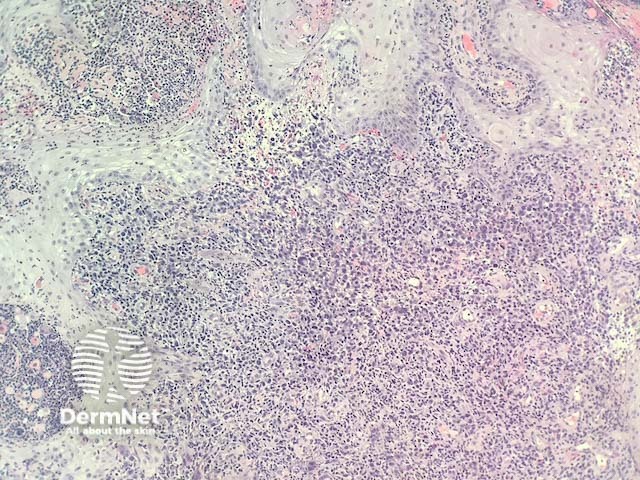

Primary cutaneous anaplastic large-cell lymphoma (pcALCL) is a rare type of indolent cutaneous T-cell lymphoma (CTCL) characterised by CD30+ atypical lymphocytes in the skin. It is classified as a primary cutaneous CD30+ lymphoproliferative disorder.

The diagnosis of primary cutaneous anaplastic large-cell lymphoma requires careful correlation of history, examination, and histopathology. Staging of pcALCL uses the TNM (Tumour, Nodes, Metastases) system.